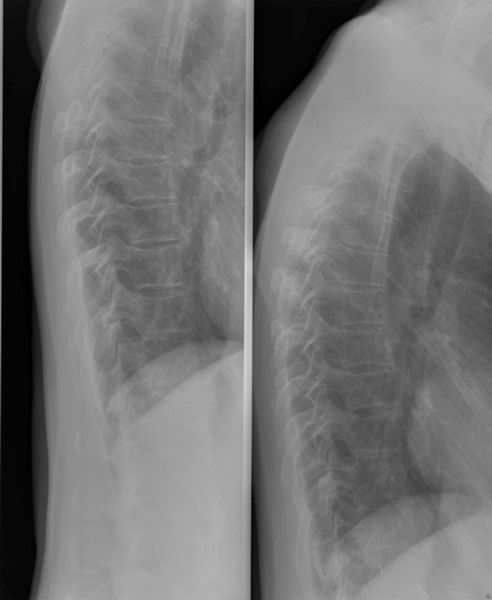

Dorsale wervelzuil